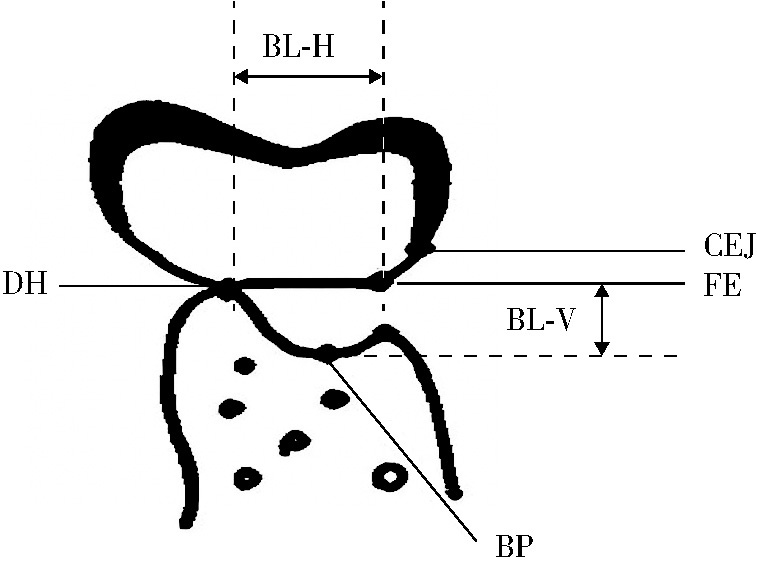

Effect of concentrated growth factors in guided tissue regeneration for the treatment of mandibular molar furcation lesions

| [14] | Fei LI,Jing QIAO,Jin-yu DUAN,Yong ZHANG,Xiu-jing WANG. Effect of concentrated growth factors combined with guided tissue regeneration in treatment of classⅡ furcation involvements of mandibular molars [J]. Journal of Peking University (Health Sciences), 2020, 52(2): 346-352. |